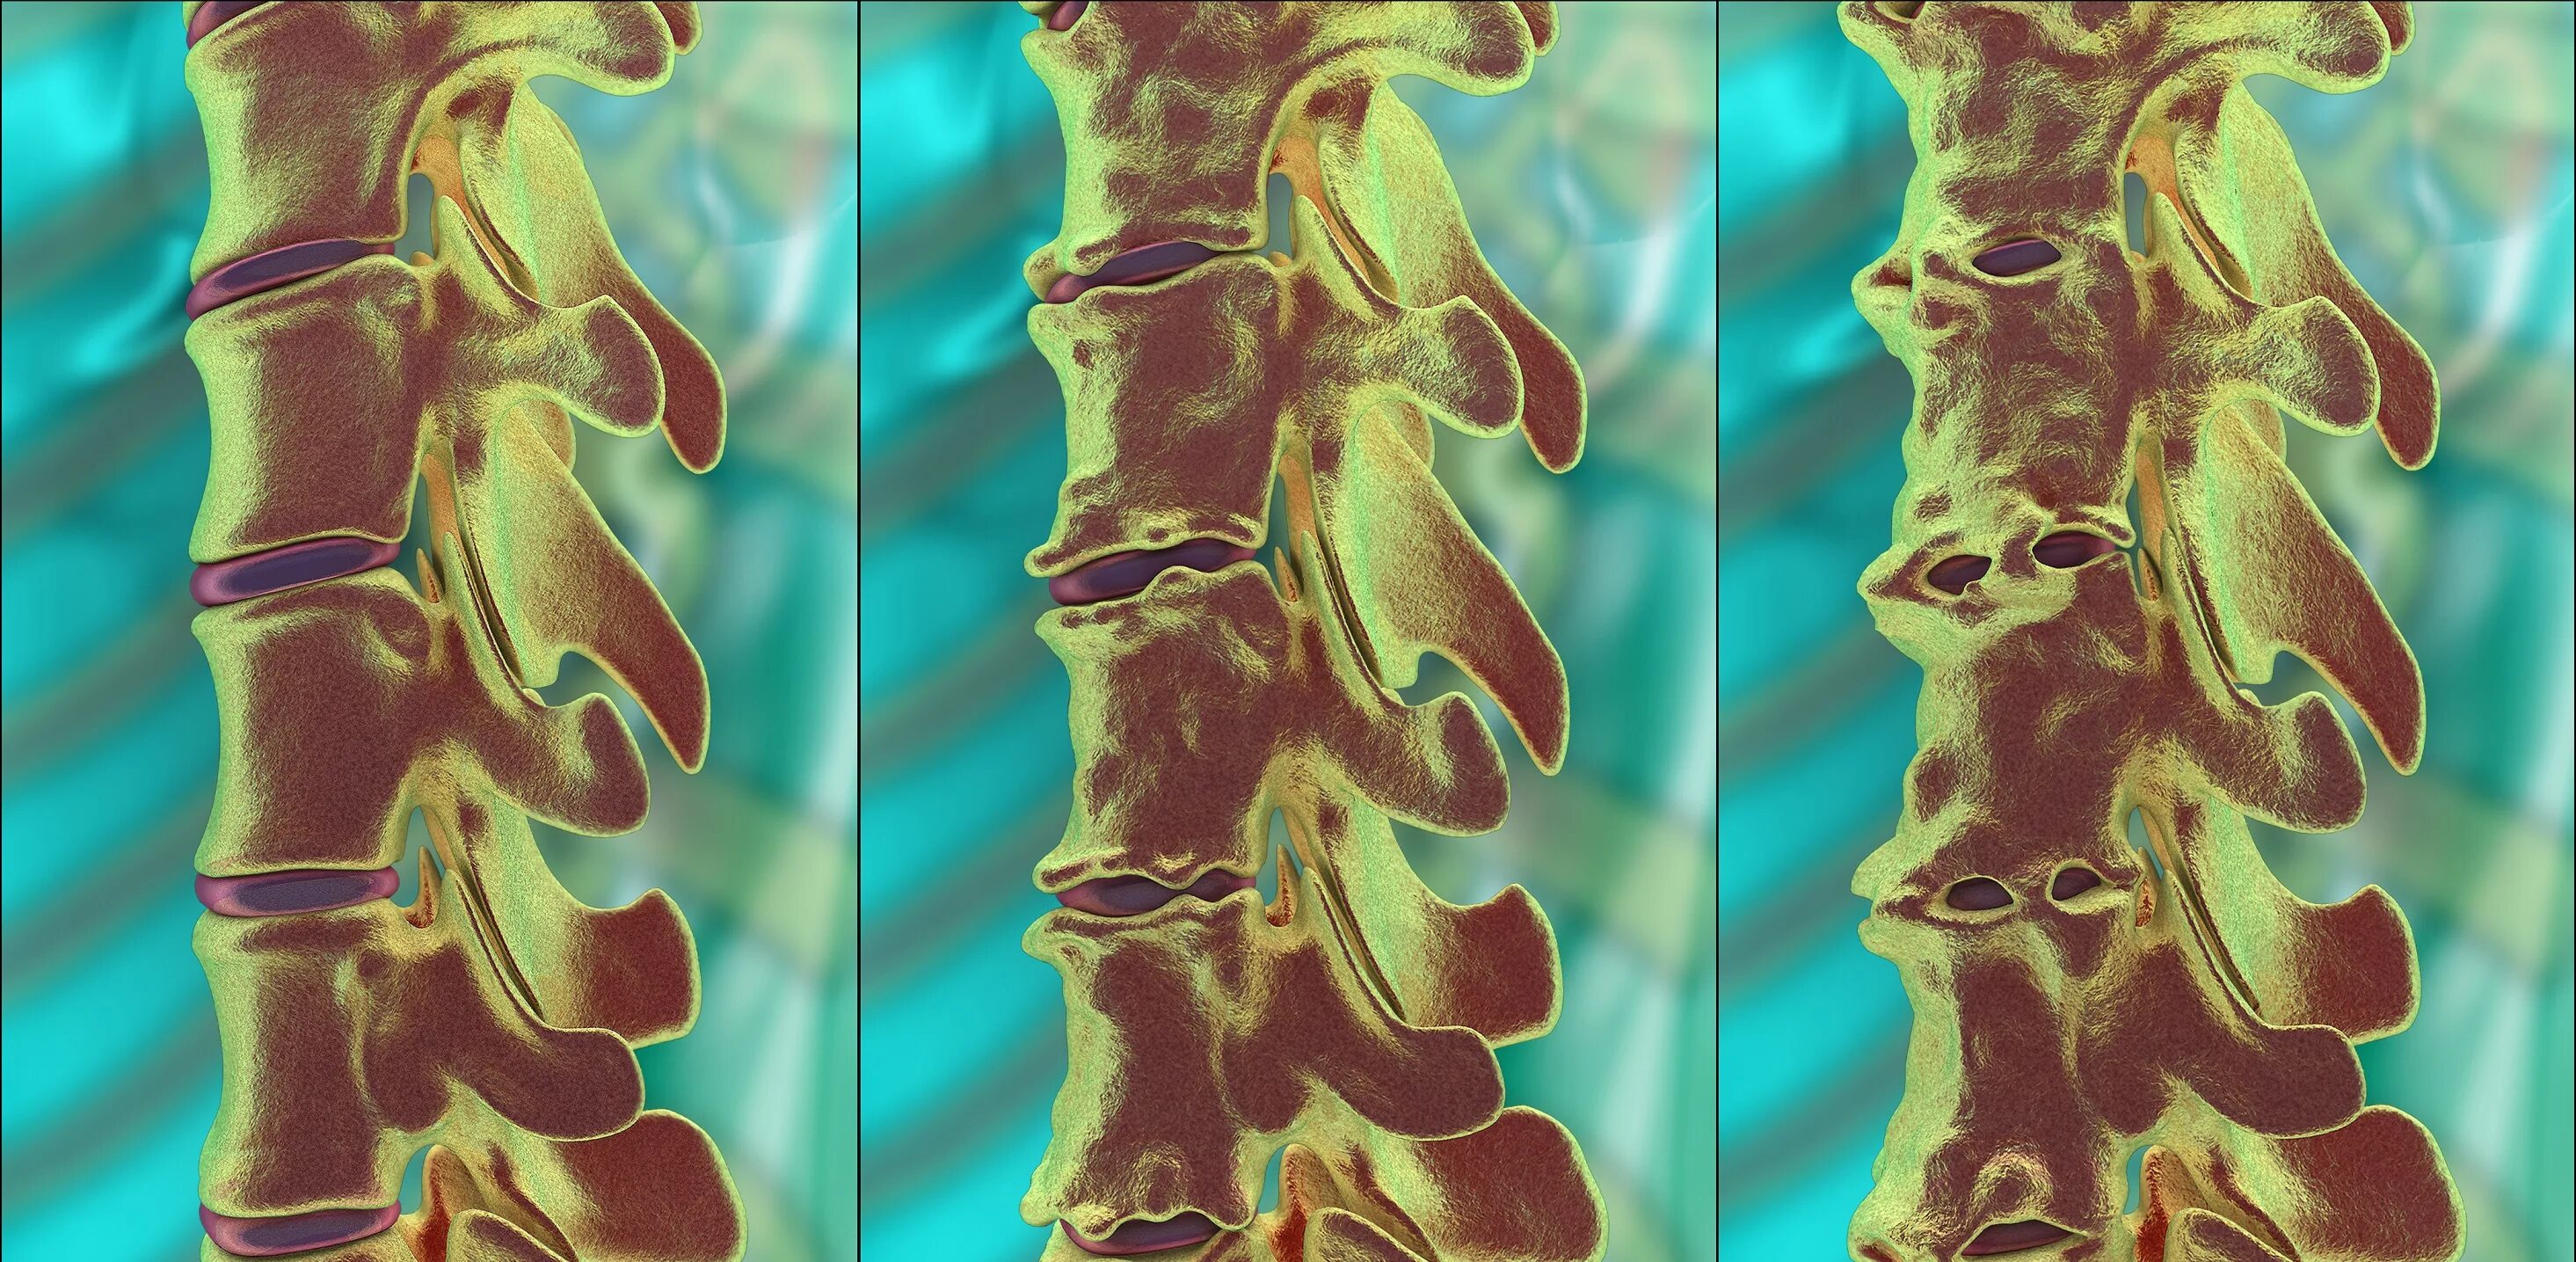

Спондилоартроз на уровне l1 s1